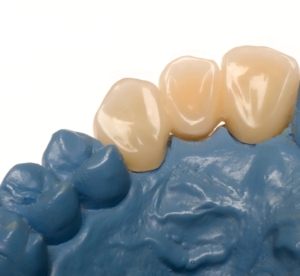

Modelo odontológico em gesso azul com coroas dentárias individuais, representando um trabalho de prótese ou restauração dentária, mostrando o que é oferecido no sistema dentista 24 horas.

Técnicas de Tratamento em Emergência

Os profissionais de odontologia especializados em urgência devem estar preparados para realizar uma série de procedimentos. Entre eles, a avaliação da condição das próteses, ajustes temporários e, se necessário, a confecção de adaptações para garantir que o paciente possa se alimentar e se comunicar sem dor. Essas intervenções são essenciais para melhorar a qualidade de vida do paciente até que uma solução definitiva possa ser implementada.